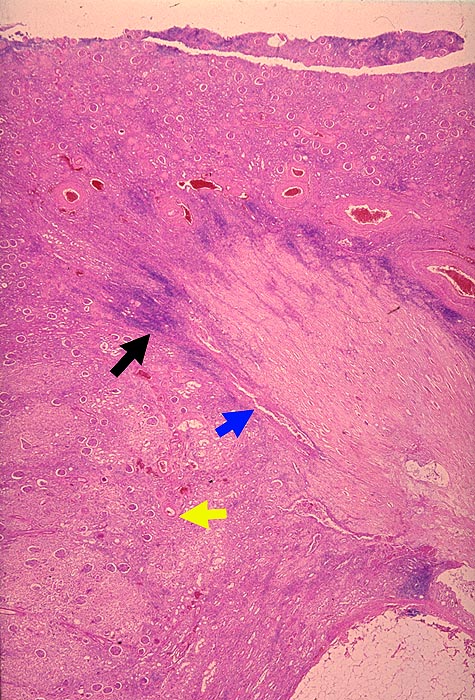

Analgetikanephropathie

Niere, Harnwege

Niere

Pathologischer Befund